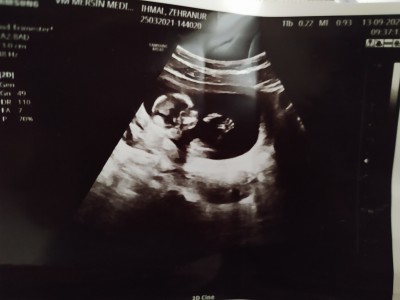

Hamilelikte cinsiyet tahmini :))

tahmin alabilir miyim

bebek-gebelik-hamilelik-cinsiyet-tahmin-

Kaç haftalık canım

13+3 haftalık